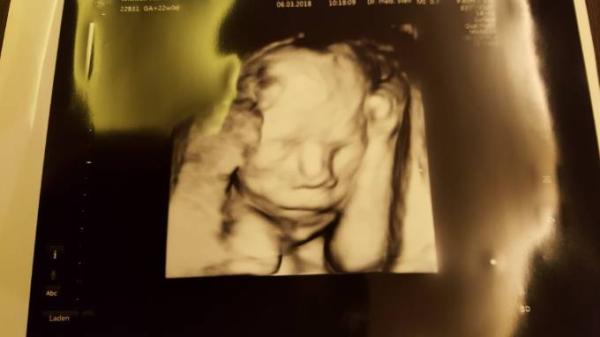

Hab eins von 22+0. Hoffe am 19.4. gibt es ein neues

Das ist aber echt süß. Ich merk schon ärmchen vorm Gesicht ist eine beliebte Position . Ich hab am 19. Auch wieder Termin. Letzter großer us